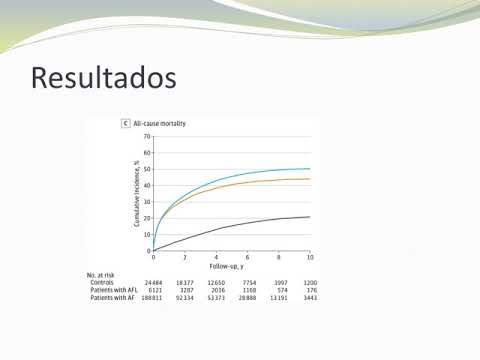

Resultados en pacientes con fibrilación auricular en cardiopatía isquémica vs no isquémica: Registro GARFIELD-AF